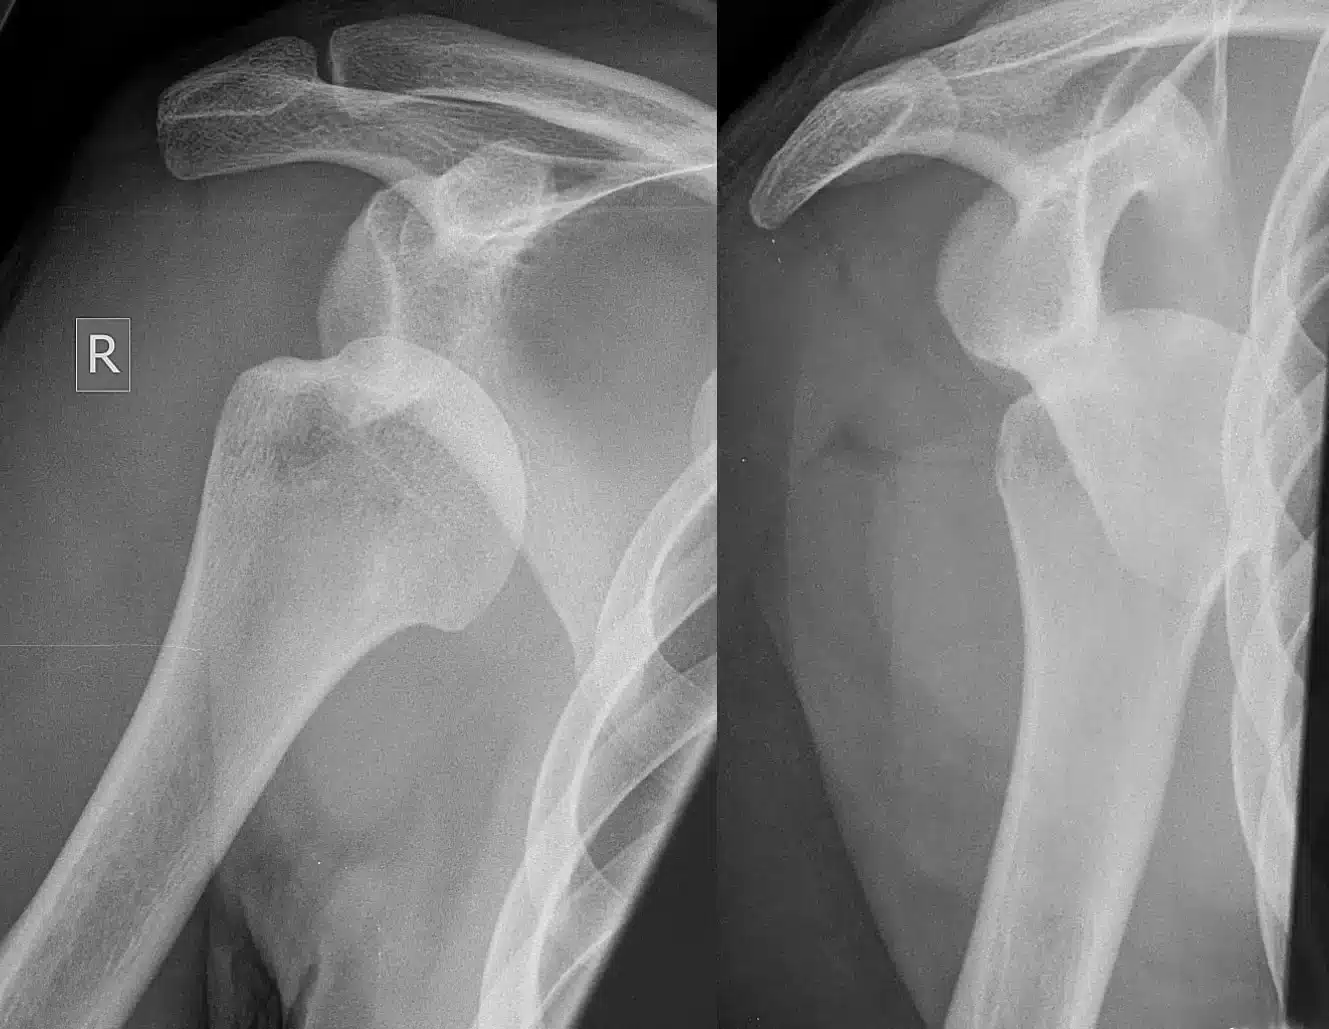

تشخیص دررفتگی شانه: معاینه فیزیکی و تصویربرداری

چگونه میتوان مطمئن شد که شانه دررفته است؟

برای تشخیص دررفتگی شانه، پزشک ابتدا یک معاینه فیزیکی کامل انجام میدهد. در این معاینه، پزشک به شانهی آسیب دیده نگاه میکند، آن را لمس میکند، و دامنهی حرکتی آن را بررسی میکند. همچنین، پزشک ممکن است از شما سوالاتی در مورد نحوهی آسیب دیدگی و علائم شما بپرسد.

برای تأیید تشخیص و بررسی آسیبهای احتمالی دیگر، پزشک ممکن است از روشهای تصویربرداری مانند:

- رادیوگرافی (اشعه ایکس): این روش میتواند شکستگی استخوانها و دررفتگی مفصل را نشان دهد.

- ام آر آی (MRI): این روش میتواند آسیب به بافتهای نرم مانند رباطها، عضلات، و تاندونها را نشان دهد.